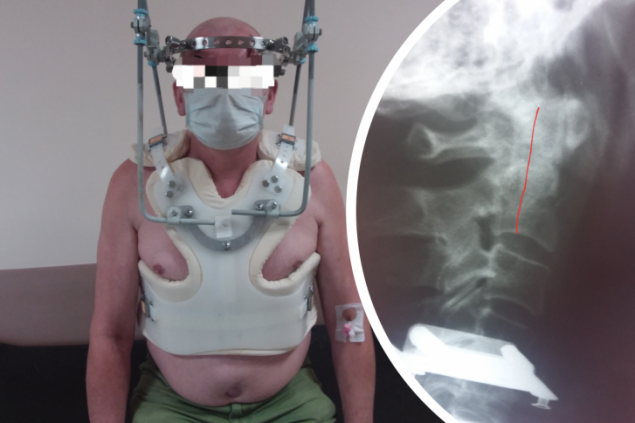

При обследовании выявилось тяжелое повреждение тела и зубовидного отростка шейного позвонка, который обеспечивает 80% движения головы. Врачи отметили, что сложность случая в том, что эта область обильно кровоснабжается, и на момент поступления в больницу у пациента уже были выраженные деформации, держать голову нормально он не мог физически.

Чтобы поставить позвонок на место, пришлось использовать специальную систему гало-фиксации: на тело установили корсет, к черепу присоединили кольцо, через корсет на туловище обеспечивается тяга, за счет которой постепенно выправляется смещенный позвонок и стабилизируется.

— Этапно мы оттрепанировали этот перелом. Пациент выписан в удовлетворительном состоянии. Но с такой конструкцией ему предстоит ходить до 2 месяцев, — отмечает заведующий отделением Константин Тутынин.